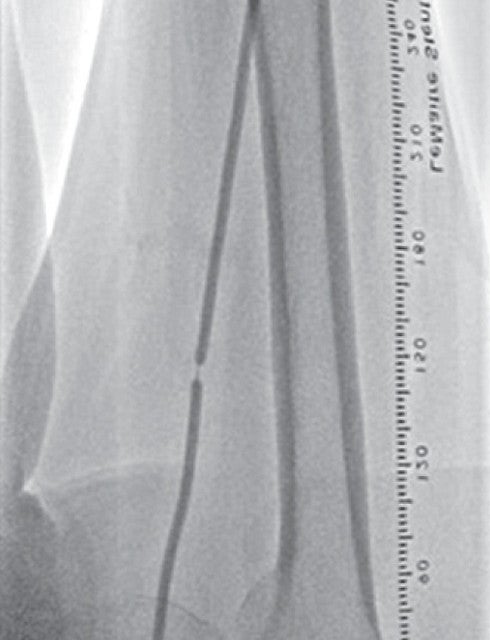

右大腿動脈穿刺、0.035 inchワイヤーを用いて、ガイディングシース 6 Fr 60 cmを左外腸骨動脈まで誘導し、造影を行った(図1.2)。体表面エコーガイドのもと、マイクロカテーテルと0.014 inch フロッピー300 cmワイヤーで、確実に浅大腿動脈入口部から血管真腔内を進めた。0.014 inch フロッピー300 cmワイヤーを抜去し、血管狭窄部貫通用カテーテルに交換し、閉塞部位を慎重に進め、貫通に成功した。血管狭窄部貫通用カテーテルにエクステンションワイヤーをつなげ、マイクロカテーテルを抜去、0.018 inchの径 2.0/長 20 mmバルーンで閉塞部位を拡張した。マイクロカテーテルを末梢まで進め、血管狭窄部貫通用カテーテルを抜去、0.014 inch 300 cm ワイヤーに交換、血管内超音波で病変部の観察を行った。ほぼ真腔を捉えていることが確認できたため、径 4.0/長 250 mmバルーンで閉塞全域を拡張した。一部石灰化病変により、拡張不良部位を認めたため(図3)、径 3.0/長 40 mm ノンコンプライアントバルーンで追加拡張を行った。再度、径 4.0/長 250 mmバルーンで閉塞全域を拡張した(図4)。血管内超音波で閉塞領域を観察し、ほぼ真腔を捉えていることが確認できた。ついで、径 5.0/長 250 mmバイアバーン® ステントグラフトを留置し、グラフト内をバルーンで後拡張した。血管内超音波でグラフト拡張および浅大腿動脈入口部を確認した(図5.6)。結果、左浅大腿動脈の良好な血流を得た(図7)。